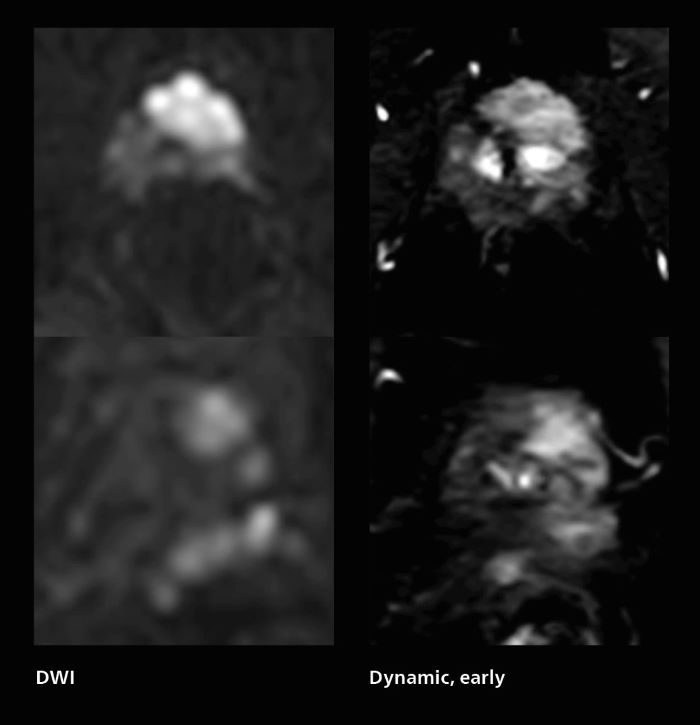

Prostate cancer MRI

MRI was performed in a patient with PSA 89.2. Evaluation of T2WI images was difficult due to rectal peristalsis. Using SmartSpeed MotionFree T2WI provided very good imaging quality. Seminal vesicle gland invasion is easily seen. Biopsy resulted in GS4+5=9. Performed on Elition X.